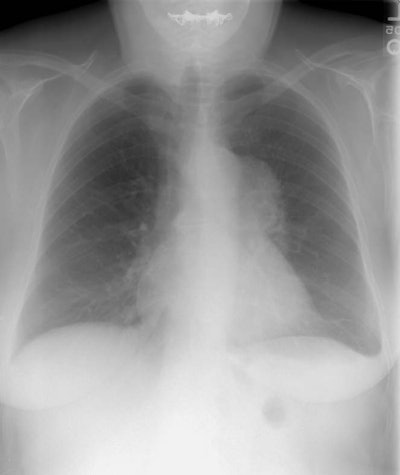

The patient below was a 57 year old female who presented with complaints of weight loss. A chest radiograph demonstrated an aortopulmonary window mass (best seen on the PA chest radiograph) and a left sided pleural effusion. (Click here if you would like to view the lateral chest radiograph). A CT scan of the chest was performed to evaluate this finding.

The chest CT demonstrated a large, low density mass in the aortopulmonary window, as well as the presence of subcarinal and left hilar adenopathy. There is a large left sided pleural effusion. At surgery the patient was found to have a Non-Hodgkins B-cell lymphoma.